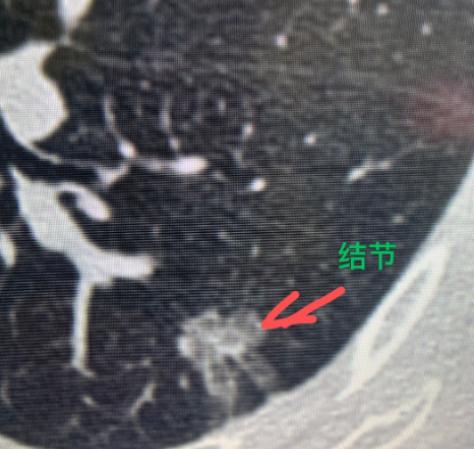

经常“拉肚子”,一查竟是肺癌......广州53岁的王姐可能怎么也想不到,自己竟然会和肺癌扯上关系!到了该体检的年纪,加上最近经常腹泻,家人便陪她做了一次全面的身体检查。 谁知道,胃肠镜结果倒没什么异常,胸部CT却发现了问题——左下肺有一个接近2厘米的结节,里面既有实性也有磨玻璃成分,形态也不太规则。 从影像上看,这个结节边缘不太平整,表面也不光滑,整体看起来有点“张牙舞爪”的样子,具备一些早期肺癌的影像特征。 和家属沟通后,为王姐做了微创手术。术后病理证实是“肺浸润性腺癌”,不过发现得还算早,通过手术完全可以达到根治,治疗效果也很好。 很多人可能会纳闷:肺癌的症状,不一般都是咳嗽、胸痛、咳血这些吗?怎么会和拉肚子有关系? 其实,有一部分肺癌细胞会分泌一些特殊的激素类物质,它们进入血液循环后,可能引起“类癌综合征”,从而表现出腹泻、关节酸痛等看似不相关的症状。不过这种情况确实不算多见。 这也提醒我们,定期体检真的很重要。尤其是45岁以上、有吸烟史、家族中有肺癌病史等高危人群,建议每年做一次低剂量螺旋CT筛查。 肺癌在早期往往没有典型症状,等到出现咳血、持续胸痛时,很多已经发展到了中晚期,治疗难度也会增大。早发现、早处理,才是应对肺癌最好的方式。[玫瑰][作揖]